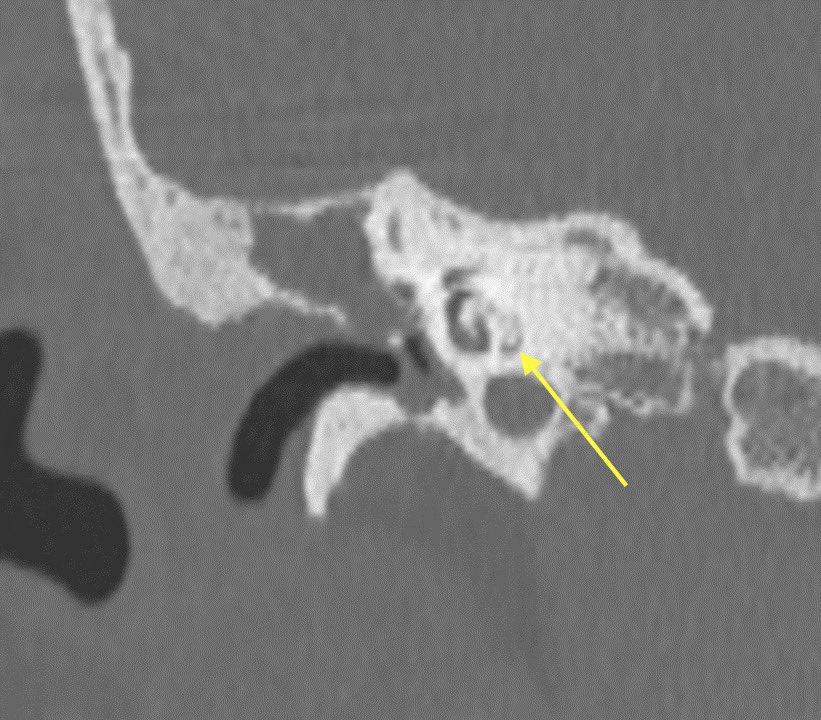

▶️CT: High density ossification of the membranous labyrinth (ignore the operative change from mastoidectomy)